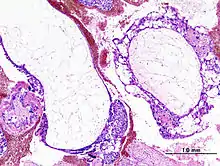

- Histopathologic image of hydatidiform mole (complete type). H & E stain.